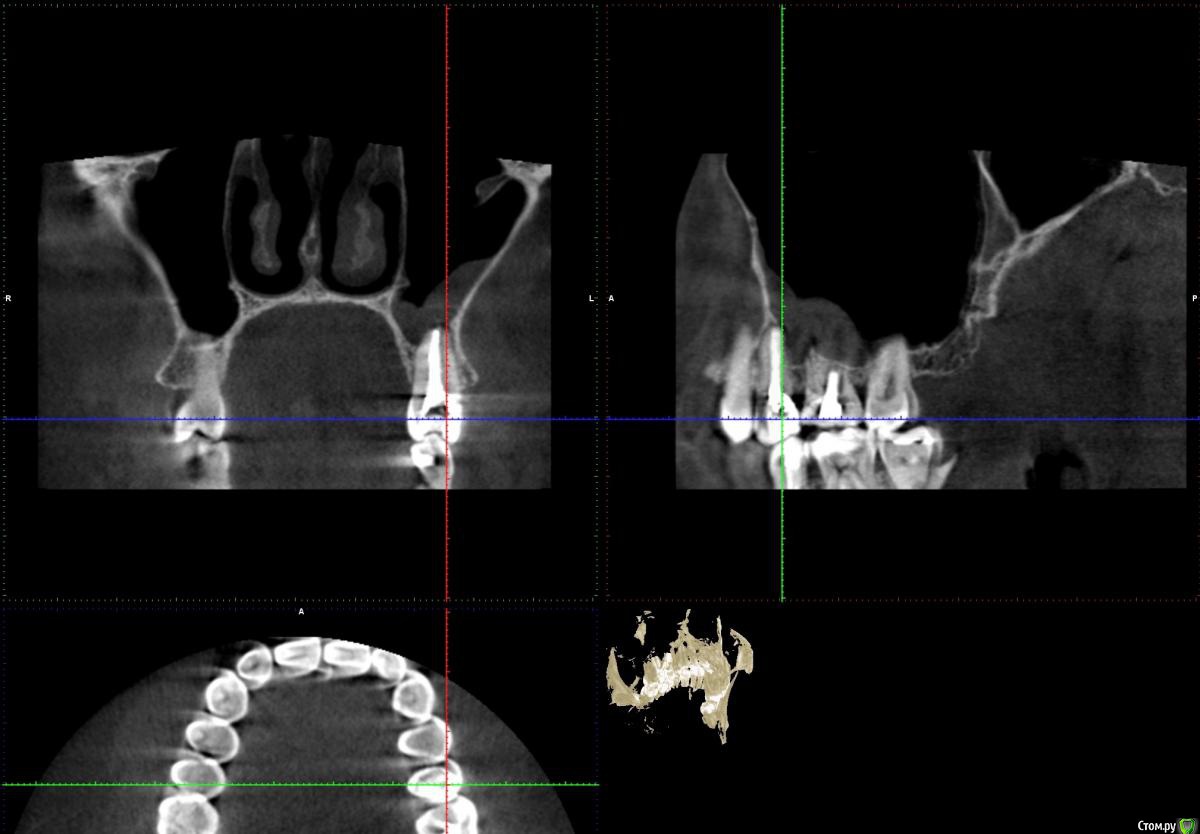

Freemind Опубликовано 13 июня, 2020 Поделиться Опубликовано 13 июня, 2020 Здравствуйте, уважаемые добрые врачи!Мне 32, мужеского полу. В начале мая обратился к своему стоматологу с жалобой на боль на холодное/горячее, точнее зуб реагировал на воду даже комнатной температуры (20-22 градуса), при надкусывании не болел. Мне казалось что это 5-й сверху слева. Он был два года назад лечен от пульпита, но сразу после лечения была странная симптоматика (хотя и пил ибупрофен 10 дней по рекомендации стоматолога): зуб не болел, не реагировал на холодное/горячее, но я его как-бы чувствовал при надкусывании/постукивании. Особого дискомфорта это не доставляло, поэтому забил и так и ходил. На приеме внешних признаков проблем не обнаружилось, сделали визиографию, увидели кисту, вскрыли зуб, три приема в течении 3- недель какие-то лечебные пасты(?) накладывали. Лучше становилось временами.Далее направил он меня на КТ. На снимках: киста оказалось над шестым, корни почти до пазух, гайморит (отчетливое воспаление, хотя из симтомов только периодические слабые головные боли в области левого виска и скудные желтовато-зеленые выделения по утрам из носа при сморкании). Этот шестой был лечен от пульпита лет 6-7 назад у другого стоматолога. Вскрыл его, обнаружил один не леченый канал (Сам я этого не вижу на КТ). Лекарство. К второму приему по 6-му зубу вроде стало получше,- на воду комнатной температуры точно перестало болеть, на откровенно холодное чаще реагирует, чем нет. Направил он меня к ЛОРу, который прописал пока назонекс, предложил варианты: 1) либо лечить зуб, смотреть динамику и далее толи 1.1.делать операцию на пазухе, толи 1.2. удалять зуб, опять смотреть. 2) сразу удалять, смотреть динамику. На сейчас: уже три раза лечебная паста(?) на 6-й. Периодически головные боли несильные, периодически реагирует на холодное и чуть поднывает. А бывает день вообще не замечаю никакого дискомфорта. Вопросы:1. На снимке киста?, есть ли перфорация? - мне кажется по снимку видно, что при лечении одного из корней (6-7 лет назад) пробита пазуха - может гайморит от перфорации, а не от кисты?.2. Почему мне субъективно кажется, что болевые ощущения когда они есть идут от 5-го, хотя киста над 6-м? Даже когда нет никаких болей, 5-й все проявляет эту странность - "как бы чувствую" его в корню (при постукивании ощущение очень отдаленно сродни щекотки).3. Стоит ли уже залечивать на постоянную эти зубы? или удалять 6-й? или сделать снова КТ сейчас? Может эта киста вообще рассосаться? Еще одно уточнение, не уверен, что относится к теме. В конце февраля было 2 дня дико плохое самочувствие - сначала только сильная ломота во всем теле, затем прибавилась температура 38. Еще пару тройку раз такое повторялось в слабой форме без температуры до середины мая. Т.е. это точно не ОРВИ была. Обследоваться начал - флюорография чистая., анализы на ВИЧ, гепатиты не успел - больницы на карантин закрылись (хотя образ жизни сильно далек от факторов риска этих инфекций). В любом случае исчезновение этих приступов ломоты совпало с началом лечения зубов - хз совпадение нет ли? С уважением, Александр. Извините за такой опус, просто что-то боязно становиться за свою тушку. P/S: вся КТ здесь https://drive.google.com/file/d/1gya4SSUk5vu8DrihvHP74CF-IKWj9XCk/view?usp=sharing. Ссылка на комментарий

St. Опубликовано 14 июня, 2020 Поделиться Опубликовано 14 июня, 2020 Добрый день. 1. На снимке киста? На снимке периодонтит, по простонародному "киста". И плюс реакция слизистой оболочки гайморовой пазухи на него. есть ли перфорация? Перфорация чего? в зубе - не видно мне кажется по снимку видно, что при лечении одного из корней (6-7 лет назад) пробита пазуха - может гайморит от перфорации, а не от кисты?. Есть немного выведенного материала, это не критично. 2. Почему мне субъективно кажется, что болевые ощущения когда они есть идут от 5-го, хотя киста над 6-м? Покажите срезы в области 5 3. Стоит ли уже залечивать на постоянную эти зубы? Имеет смысл попробовать и посмотреть на динамику. через 6 мес сделать контрольные снимки. сделать снова КТ сейчас? Раньше 6 мес после постоянной пломбировки каналов не имеет смысла Может эта киста вообще рассосаться? Да 2 Ссылка на комментарий

Freemind Опубликовано 16 июня, 2020 Автор Поделиться Опубликовано 16 июня, 2020 Огромное Вам спасибо! Покажите срезы в области 5 Ссылка на комментарий

St. Опубликовано 16 июня, 2020 Поделиться Опубликовано 16 июня, 2020 Я бы начинала перелечивание с 6, если дискомфорт пройдет, то ок. Если нет, то перелечивать и 5 ( по кт канал заполнен на всю длину вполне плотно, но кость за пределами корня неоднозначная..) Ссылка на комментарий